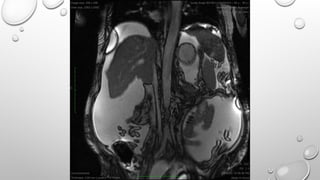

IN PHASE OUT OF PHASE IMAGING

• BESIDES THE DIFFRENCE IN T1 RECOVERY AND T2 DECAY TIMES OF FAT AND WATER PROTONS,

ANOTHER IMPORTANT DIFFRENCE BETWEE THE TWO IS DIFFRENCE IN RESONANCE FREQUENCY

WHICH IS RELATED TO DIFFERENT ELECTRONIC ENVIRONMENTS – WATER AND FAT PROCESS AT

DIFFERENT FREQUENCIES WHICH CAUSES THE PHASE SHIFT BETWEEN THE TWO. THIS PHASE

SHIFT OSSCILATES WITH PERIODICITY SUCH THAT AT 1.5 T, WATER AND FAT PROTONS WILL BE

IN PHASE AT AN ECHO TIME OF 4.4 msec AND WILL BE OUT OF PHASE AT 2.2 msec BEFORE

AND AFTER THE FIRST PHASE TE. THUS VOXELS THAT CONTAIN BOTH FAT AND WATER WILL

HAVE ADDITIVE SIGNAL AT THE IN PHASE TE AND WILL HAVE CANCELLATION OF SIGNAL AT

THE OUT OF PHASE TE.

TECHNIQUE

1. THE TYPICAL CHEMICAL SHIFT MRI SEQUENCE IS T1 WEIGHTED SPOILED DUASL GRADIENT

ECHO SEQUENCE

2. IT IS USED WITHOUT FAT SUPRESSION TO AVOID MASKING INDIAN INK ARTEFACT AND

BEFORE THE ADMINISTRATION OF IV CONTRAST TO AVOID ALTERATIONS IN T1 SIGNAL

INTENSITY THAT MAY OBSCURE CHEMICAL SHIFT SIGNAL INTENSITY LOSS.

3. THE IN PHASE AND OUT OF PHASE IMAGES SHOULD BE VIEWED SIMULTANEOUSLY ON A

SINGLE MONITOR TO AVOID ARTIFACTUAL DIFFERENCE IN SIGNAL INTENSITY.